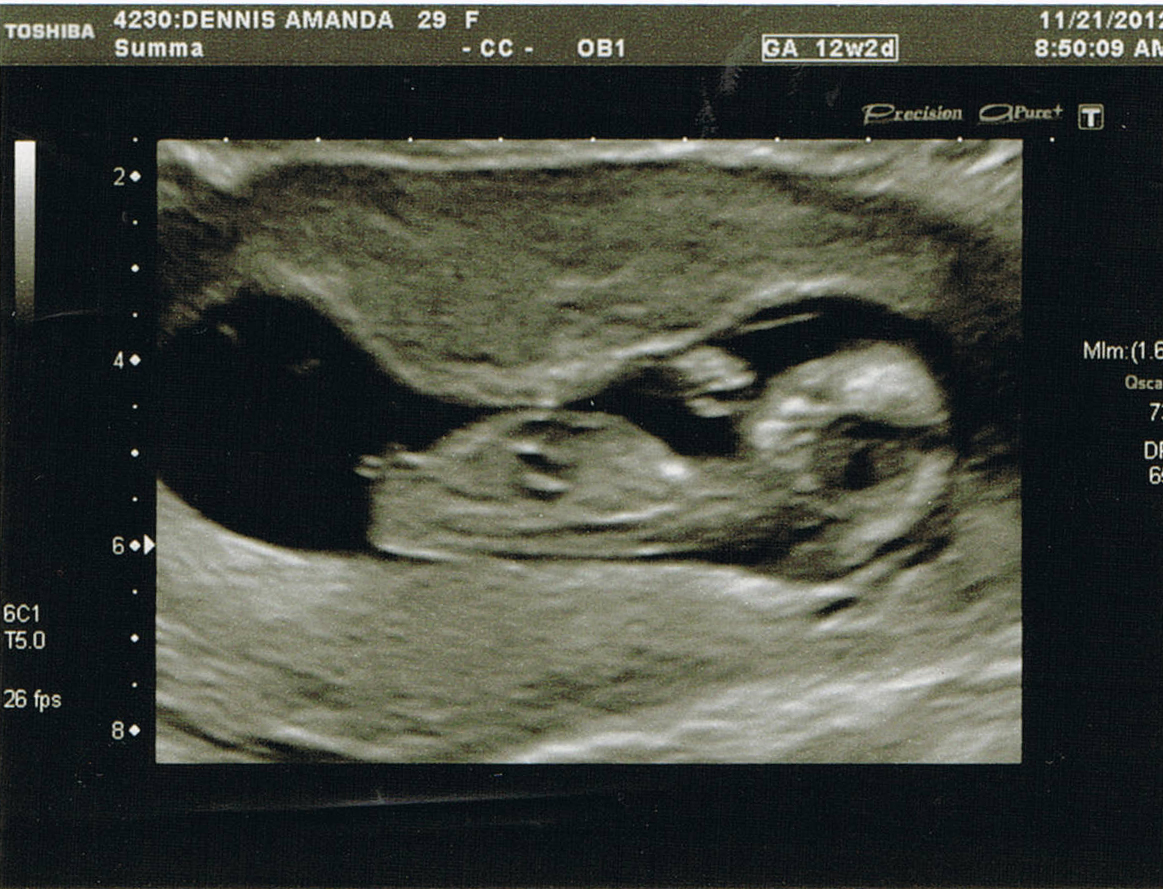

12+2 nub pic! update: it's a...?